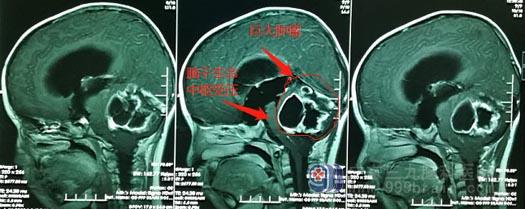

▲佳佳影像检查

鲁明接诊时,发现患儿神志清醒,但精神状态比较差,不能正常走路。结合影像检查和临床病症,鲁明认为患儿颅内肿瘤的诊断明确。在显微镜下,鲁明为患儿实施毛细胞星形细胞瘤切除手术,成功摘除一颗大小约6.4cmx5.9cmx5.6cm的肿瘤,足有鸭蛋般大小。术后病理提示是(小脑蚓部)毛细胞星形细胞瘤,WHO I级。